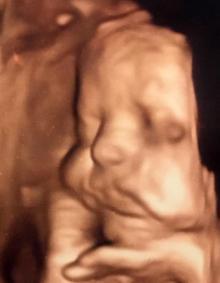

"Bazı bebekler, annelerini sabah erken saatlerde takip ettiğimizde uykulu halde olur. Güzel poz yakalayamayız. O zaman anne adayına 'öğleden sonra tekrar gel' derim. Bebeklerin ruh hallerini rahatlıkla görebiliriz. Mutlu bebekler, gülen bebekler, sinirlenip muayeneyi sevmeyen bebekler var. Beni itmek isteyip eliyle yüzünü kapatan bebekler de var. Bebeklerin el ve ayakları genellikle yüzlerinin önünde olduğu için her zaman güzel pozlarını yakalayamayabiliriz. Bir güzel poz için birkaç muayene gerekebilir. Yüzünü asmış tontiş bebekler var. Bazı bebeklerin yanakları çok net güzel görünür. Aynı pozu doğum sonrası da görebiliriz. Ayağını gösteren bebekler var. Parmağını emen bebekler var. Düşünceli bebekler var, elini çenesine dayamış olarak poz veren bebekler var."

Anne adaylarının muayenelerinde ultrason görüntülerini alırken kimi zaman sinirli bebeklerle karşılaştıklarını anlatan Op. Dr. Aksu, "Bazı bebekler de kendini hiç göstermek istemez. Adeta 'Bakma bana' der. Elleriyle yüzlerini kapatırlar adeta. Tabi bebeklerin de mahremiyeti var. Eğer onlar kendilerini göstermek istemezse ben de geri çekilirim. Zorlamam" diye konuştu.